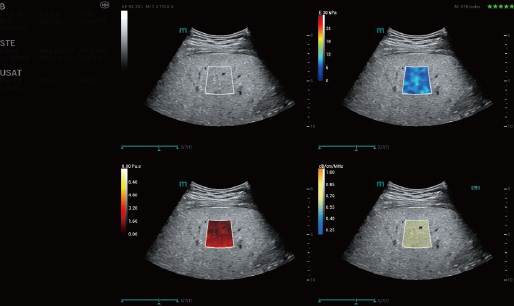

STVi consente la valutazione quantitativa della viscosit├Ā dei tessuti e fornisce immagini multiparametriche in tempo reale, offrendo un approccio pi├╣ completo alla diagnosi per immagini e all'analisi quantitativa di malattie epatiche croniche, lesioni mammarie e altre condizioni.

Valutazione della malattia epatica cronica

Strumenti di quantificazione multipli